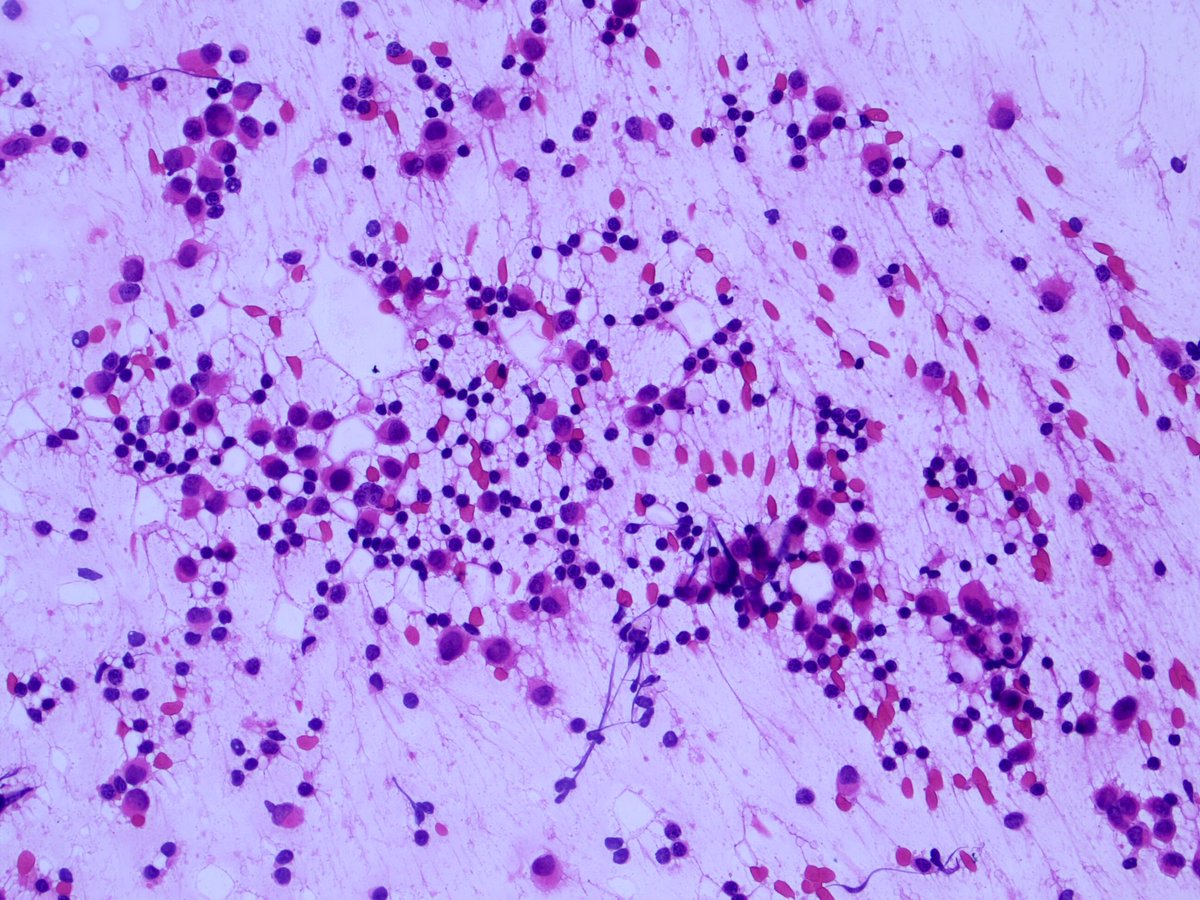

Intraoperative sentinel node touch prep shown. If cancer —> axillary dissection.

Diagnosis? Comments encouraged. Histology correlation and discussion to follow.

1. Discussion: Interesting voting trend. “Benign” held the early slight majority, then some astute people suggested metastatic lobular carcinoma. The voting them swung decidedly towards “cancer”!

6. Some annotated images showing the atypical features of the red box cells above.

None of these are specific; histiocytes may resemble lobular cancer cells. However, taken together, these atypical features should raise concern for malignancy, and prompt a frozen section.